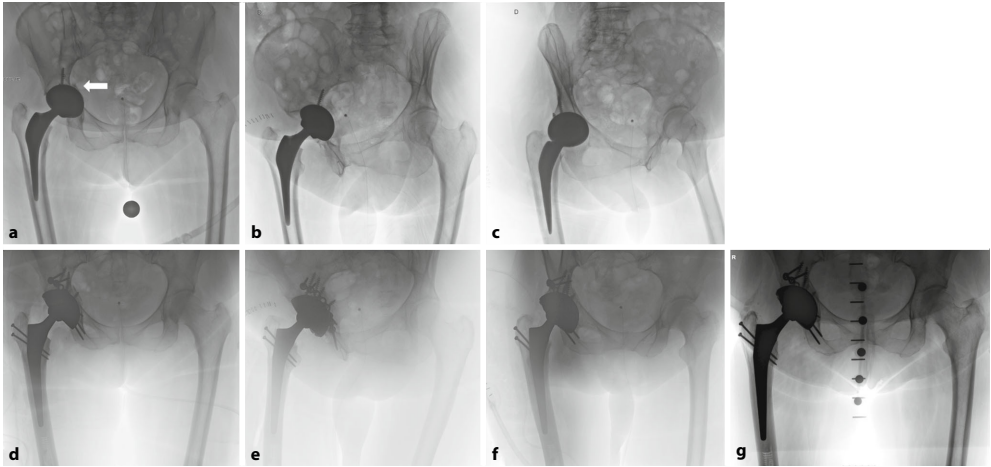

针对全髋关节置换术后日益增多的假体周围髋臼骨折(PPAF)这一复杂并发症,瑞士伯尔尼大学团队系统综述了基于Letournel分型的治疗策略。研究提出结合术前CT评估、AAOS/Paprosky分型及UCS分类的综合性诊疗路径,确立以植入物稳定性为核心的决策算法,为同时需要骨折修复和翻修技术的复杂病例提供了循证指导。